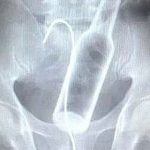

Röntgen filmlerinden akıl almaz

Tarih: 25.02.2025 13:01